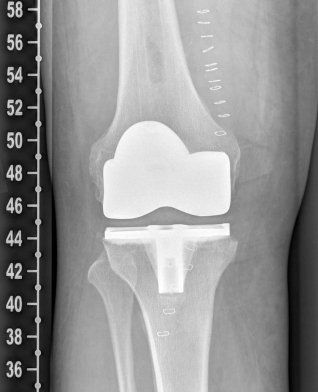

Example X-ray images before and after implantation of a Persona knee prosthesis with robot.

Röntgenbild nach OP von vorn Röntgenbild nach OP von seitlich

b) nach Implantation der Knie-Totalendoprothese angefertigte Röntgenaufnahmen